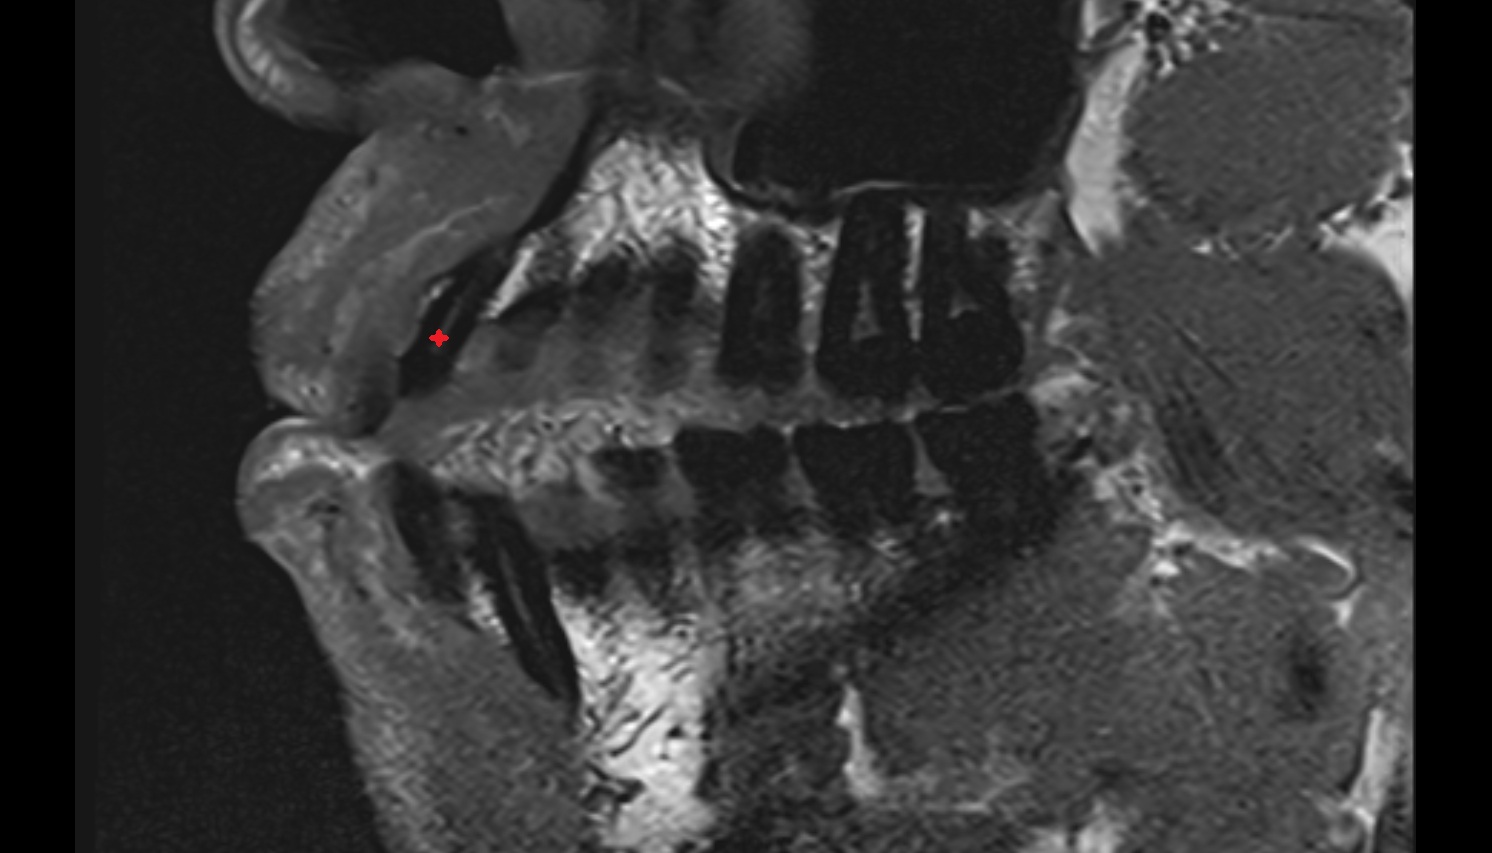

- Anterior Band of Articular Disc TMJ

- Posterior band of articular disc, TMJ

- Articular capsule of temporomandibular joint

- Articular disc of temporomandibular joint

- Articular eminence

- Articular surface of mandibular fossa

- Articular tubercle

- Intermediate zone of articular disc

- Lateral temporomandibular ligament

- Superior retrodiscal layer

- Superior synovial membrane of temporomandibular joint

- Temporomandibular joint

- Mandibular condyle

- Mandibular fossa

- Neck of mandible

- Ramus of mandible

- Zygomatic process of temporal bone

- Deep part of masseter muscle

- Superficial part of masseter

- Superior head of lateral pterygoid muscle

- Inferior head of lateral pterygoid muscle

- Lateral pterygoid muscle

- Masseter muscle

- Medial pterygoid muscle

- Temporalis muscle